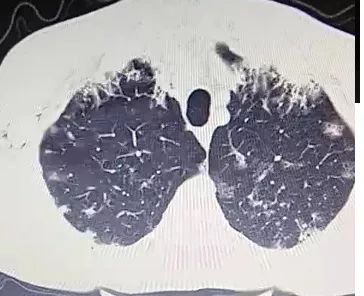

下面这个CT,乍一看,是不是毫无头绪?

然而,当病人说每天咳痰两三碗,大约200~300ml(1市斤500ml),而且是经常这样的时候,我突然眼前一亮,莫非是?

抗感染治疗,痰量增多。CT如下,没有什么特殊的。

■ 北京大学第一医院呼吸内科报道1例,每天咳痰多达500ml,外院抗感染治疗无效。给予靶向药吉非替尼治疗,痰量减少。CT如下,没有什么特殊的。

CT,双肺弥漫性病变(多发斑片、结节影、磨玻璃影),如下: